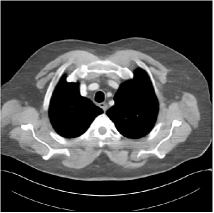

Fig. 3: Three examples (from top to bottom) of the reconstructed testing images using Momentum-Net with SimpleCNN (the second column), with SimpleCNN-RSN (the third column), and with Dn-RSN (the fourth column). The compared WavResNet denoised images are shown in the first column, and the reference images are in the fifth column. See their FBP images in Fig. 4.

Fig. 4: FBP images of test examples.

Fig. 2 shows that the proposed Momentum-Net with SimpleCNN decreases RMSE dramatically in the first 30 layers, and tends to converge in 50 layers. The Momentum-Net reduces the mean RMSE value by 4.5 HU and gives smaller standard deviations in RMSE, compared to WavResNet, as reported in Table 1. This implies that the proposed Momentum-Net with SimpleCNN can improve both the accuracy and stability of low-dose CT image reconstruction than a state-of-the-art image denoising deep NN, WavResNet. The proposed Momentum-Net with SimpleCNN better removes noise and streak artifacts than WavResNet. It also provides clearer reconstructions of some details; see, in Fig. 3, the boundaries shown in the zoomed region at the top-right corner in the first example, the arrow pointed structures in zoomed areas of the second example, and the arrow pointed tissues in the left zoomed region in the third example.

We show the reconstructed examples by Momentum-Net with SimpleCNN-RSN and Dn-RSN in the third and fourth columns of Fig. 3 respectively. Comparing the first three and the last columns in Fig. 3, we observe that Momentum-Net with SimpleCNN-RSN provides generally noisier reconstructions than WavResNet and Momentum-Net with SimpleCNN. However, Momentum-Net with SimpleCNN-RSN sometimes can provide clearer details than WavResNet. For example, in the right zoomed box of the second example, Momentum-Net with SimpleCNN-RSN shows better reconstruction quality for the arrow pointed structures than WavResNet, and in the left zoomed box in the third row, the former gives clearer small tissues marked by red arrows than the latter. Table 1 reports that Momentum-Net with SimpleCNN-RSN is approximately 2.9 RMSE (HU) higher than WavResNet, while it has smaller standard deviations. This implies that Momentum-Net with SimpleCNN-RSN is more stable than WavResNet, although it may not provide better image qualities. Momentum-Net with Dn-RSN, however, provides the worst visual and numerical results among the compared four methods in this paper.